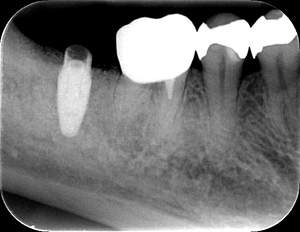

インプラント治療の症例1

レントゲン写真

- 透過像

| 年齢 | 50代・男性 |

| 主訴 | 右下歯が疼く |

| 治療内容 | ・右下6番インプラント ※1:FGG(遊離歯肉移植術)とは、足りない歯ぐきを上顎から上皮を切り取り移植する外科手術 |

| 治療費 | 合計:902,000円(税込) ■内訳 |

| 治療期間 | 9ヵ月 |

| 治療方針 | 右下の当該歯は歯根破折により保存不可能と診断しました。歯周疾患も伴っていたため抜歯後に骨吸収※1が大きく起こることが予測できました。チタンメッシュ併用骨再生誘導法(GBR※2)を選択しインプラント埋入と同時に行い自然な歯槽骨のラインを再現しました。またGBRを行う際にインプラント辺縁の付着歯肉の減少が起こる為、遊離歯肉移植術(FGG※3)を行い清掃性を考慮した形態に仕上げました。 ■治療方針の解説 治療した右下の歯をレントゲンで撮影したところ根本の部分に黒く写る箇所があり「根尖性慢性周囲炎※1」と診断。また歯周病も進行していました。 ※1 骨吸収・・・歯槽骨という歯を支える骨がなくなっていくこと |

| 担当者所見 | 主訴の右下だけでなく歯茎の腫れ、発赤があり不良補綴や不良充填など他にも治療箇所が多数ありました。プラークコントロールが不良であった為まずはブラッシング指導を行いセルフケアの重要性を理解していただくところからスタートしました。 右下6番の歯はインプラント治療を行なった結果審美的にも機能的にも患者様の満足を得ることができました。骨造成と歯肉移植も行なった為インプラントを支える十分な歯周組織の獲得ができたと思っております。 |